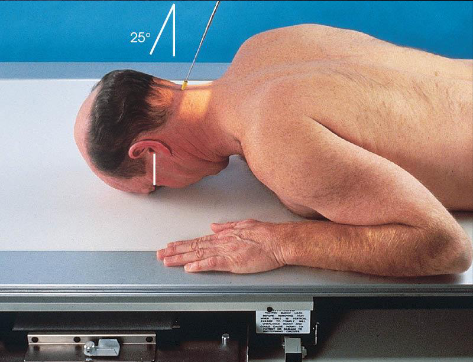

PA axial (Haas) skull

patient position:

prone or upright

MSP centered to midline

shoulders in same horizontal plane

part position:

forehead and nose resting on Bucky/table

MSP perpendicular to IR

OML perpendicular to IR

respiration suspended

CR:

25 degrees cephalad to OML

enters 1 ½ inches below external occipital protuberance

exits 1 ½ inches superior to nasion

collimation:

1 inch beyond the skin line of the skull

PA axial (Haas) skull image criteria

projection of dorsum sellae and posterior clinoid processes within foramen magnum

equal distance from lateral border of skull and lateral margin of foramen magnum

symmetric petrous pyramids

entire cranium